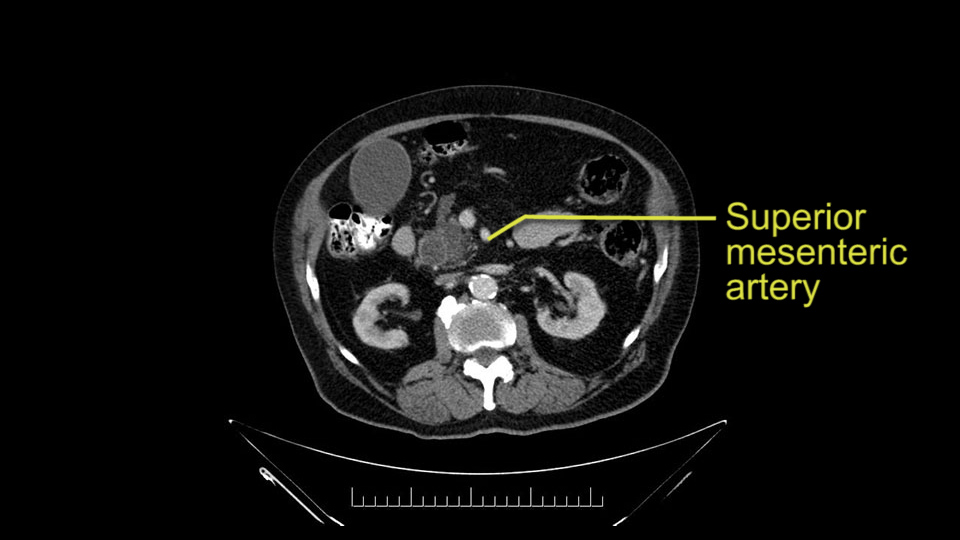

Then either through the coronal or the axial, I’ll do both. Look at the SMA -which is here- I had already looked at it and I don’t see any involvement. There’s the SMA with a nice fat plane between the SMA and the tumor. Over here you can see on the axial, there’s the SMA. Everything on the right side of the SMA has got some nice black around it, which is fat, which means probably no tumor [no tumor, no tumor]. Follow it up to the origin, coming off the aorta. So those are the two technical things that I worry about: the SMA and the SMV.

To plan a pancreatoduodenectomy, we start by reviewing the vascular anatomy, especially the origin of the celiac trunk, here, in front of the aorta, looking for any evidence of stenosis. In addition, we look at the origin of the superior mesenteric artery, to look for any branches, and any replaced right hepatic arteries coming from the superior mesenteric artery; which does occur in about 12% of the population.

Other important points are: the dissection of the uncinate process which must be done very carefully, the ligation of the venous branches there, and looking for the inferior pancreaticoduodenal arteries coming from the superior mesenteric artery during the dissection of the uncinate process.

Once the pancreatic neck is divided, you sort of roll or flip the neck of the gland over, exposing the anterior surface and the right lateral surface of the portal vein-SMV complex. Continue that dissection down. Oftentimes you can really continue your dissection right along the uncinate on the SMA. Again a little advantage of this patient having an ampullary lesion, there's likely to be no evidence of extension into the uncinate so you don't have to worry quite as much about the margin at the uncinate as you would with a pancreatic head cancer. Keeping in mind that you will have an inferior pancreatic duodenal artery in there that you want to try to identify and ligate individually. At some point along that time I go to the ligament of Treitz. Clean an area of the ligament of Treitz of its mesentery, divide it there with a linear stapler. I use the Harmonic scalpel to mobilize the proximal 10-inches or so of small intestine down to the ligament of Treitz completely mobilize the ligament of Treitz past the jejunal limb underneath the root of the mesentery and then carefully dissect the third and fourth portion of the duodenum’s mesentery as well as the remaining uncinate to complete my resection. I will have marked and sent frozen section from the pancreatic neck at the time that I do the resection of that part of the gland so that I have that information back by now. I would also probably get a margin on the uncinate and a margin on the bile duct just for completeness, although for an ampullary carcinoma that would be unlikely to have a positive extension.